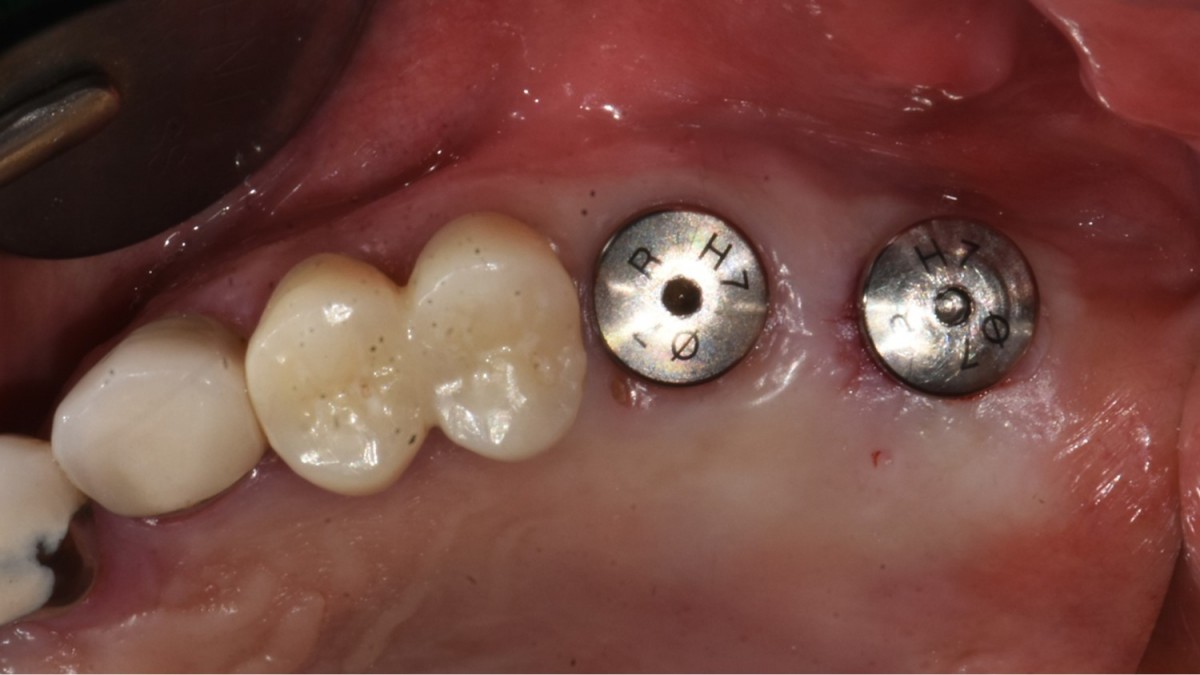

A 57-year-old male patient recently underwent

implant restoration on the maxillary right molar. This time, he is scheduled to

proceed with the left molars. (ARUM implant system)

▲2 implants were placed. ArumDentistry NB1 5*10 (30Ncm) in the 1st molar and 5*10 (10Ncm) in the 2nd molar.